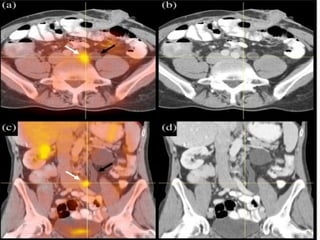

Positron emission tomography (PET) scan

For a PET scan, a form of radioactive sugar (known as fluorodeoxyglucose or FDG) is injected

into the blood. The amount of radioactivity used is very low. Cancer cells in the body grow

rapidly, so they absorb large amounts of the radioactive sugar. After about an hour, you will be

moved onto a table in the PET scanner. You lie on the table for about 30 minutes while a special

camera creates a picture of areas of radioactivity in the body. The picture is not finely detailed

like a CT or MRI scan, but it provides helpful information about your whole body.

A PET scan can help give the doctor a better idea of whether an abnormal area seen on another

imaging test is a tumor or not. If you have already been diagnosed with cancer, your doctor may

use this test to see if the cancer has spread to lymph nodes or other parts of the body. A PET scan

can also be useful if your doctor thinks the cancer may have spread but doesn't know where.

Special machines are able to perform both a PET and CT scan at the same time (PET/CT scan).

This allows the doctor to compare areas of higher radioactivity on the PET with the more detailed

picture of that area on the CT.

CT- PETCT- PET